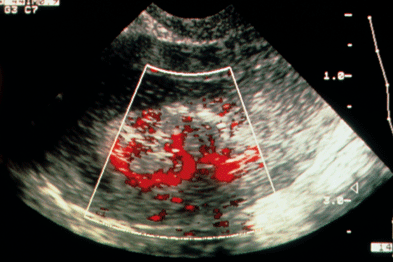

Cervical Polyp Of Uterus- Ultrasound And Color Doppler ...

Cervical polyp seen on transvaginal ultrasound and color Doppler ultrasound imaging of the uterus. See: http://www.ultrasound-images.com/uterus/#Pedunculated ... View Video

The Role Of Ultrasound In The Assessment Of Uterine Cervical ...

Notwithstanding, in the last few years, ultrasound has gained attention as an imaging technique for evaluating women with cervical cancer. In this paper, current knowledge about the use of ultrasound for assessing uterine cervical cancer will be reviewed and discussed. ... Read Full Source